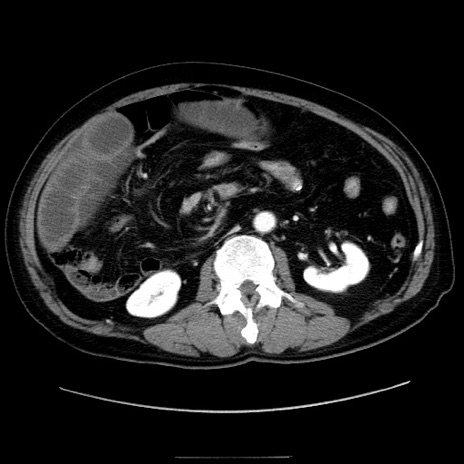

症例30(横断像)

【症例】80歳代男性

【主訴】臍周囲痛

【現病歴】約6時間前から臍下部痛が出現。次第に腹部膨隆・背部痛も生じてきたため来院。背部痛の場所は変化しない。

【身体所見】意識清明、BT 36.3℃、BP  131/87mmHg、P 87bpm、SpO2 100%(RA)、臍周囲自発痛・圧痛あり、反跳痛なし、自発痛部位に一致して板状硬あり、腹部膨隆、腸雑音減弱、CVA tenderness両側陰性。

【データ】WBC 19600、CRP 0.33